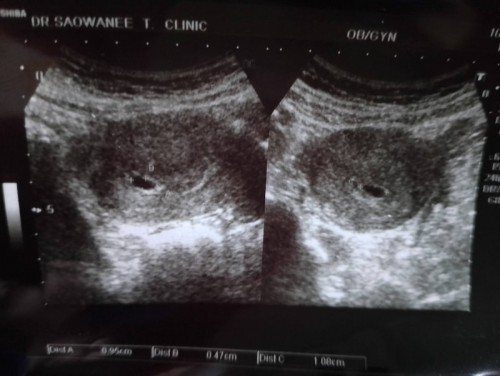

ตอนนี้ตั้งครรภ์7w+4 มีเลือดออกเหมือนประจำเดือน อันตรายมั้ยค่ะ

มีเลือดออกเหมือนเป็นประจำเดือน มีมูกใสปนเลือดบ้างบางครั้ง แต่ไม่มากนะคะ เป็นมา1อาทิตย์แล้วค่ะ ไม่มีอาการปวดท้องใดๆ จะแท้งมั้ยค่ะ##ขอคำแนะนำหน่อยค่ะ #คุณแม่ๆช่วยแนะนำหน่อยค่ะ #ขอบคุณล่วงหน้านะคะ #ขอบคุณสำหรับคำตอบค่ะ